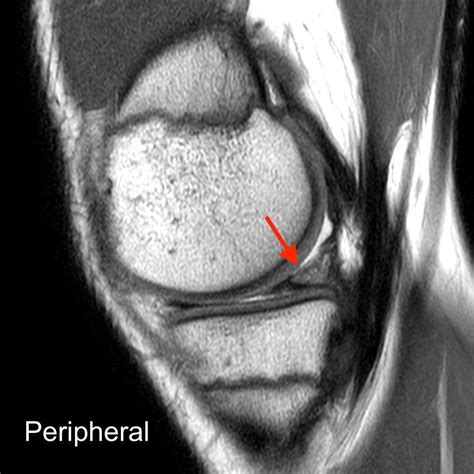

• Magnetic Resonance Imaging (MRI) to provide detailed images of the meniscus and surrounding structures. MRI is particularly useful in identifying the location and extent of the tear.